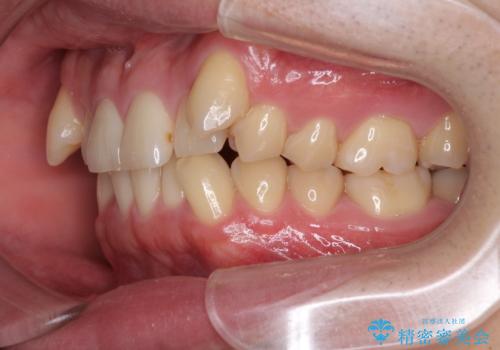

- 上顎の八重歯と前歯のデコボコを気にして来院された患者様です。

八重歯の移動量が多く、インビザライン単体での治療は困難と判断し、補助装置により八重歯移動後にインビザラインを用いることとしました。

上顎のみの抜歯矯正をインビザラインで行う場合、奥歯の前方移動がインビザラインでは苦手のため、奥歯の咬み合わせが不十分となることがあります。

今回の治療では終了時に奥歯は接触しているものの、接触の程度は物足りないものがある状態でした。今後保定期間に少しずつ奥歯の咬合を改善させていくことになります。